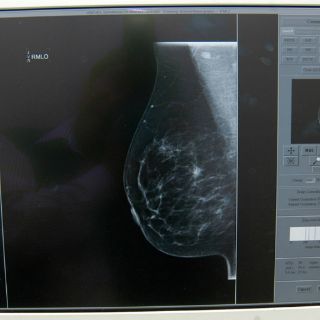

El especialista del Instituto Mexicano del Seguro Social (IMSS) en Jalisco señaló que aún cuando la autoexploración y estudios como ecografías y mastografías posibilitan la detección temprana del cáncer de mama, existen alternativas profilácitcas (preventivas) como la mastectomía subdérmica.

Destacó que toda mujer posterior a una mastectomía subdérmica debe continuar con revisiones médicas periódicas "cada seis meses o cada año, en función de la intensidad del riesgo y esto significa la realización de ecosonogramas y mamografías".

Existen técnicas radiológicas que con tomas desde diferentes ángulos pueden captar tejido residual, lo importante es que estas pacientes no se descuiden, enfatizó el especialista.